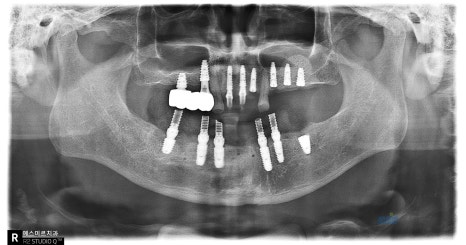

์์ ํ ํ๋ ธ๋ผ๋ง์ ๊ตฌ๊ฐ์ฌ์ง